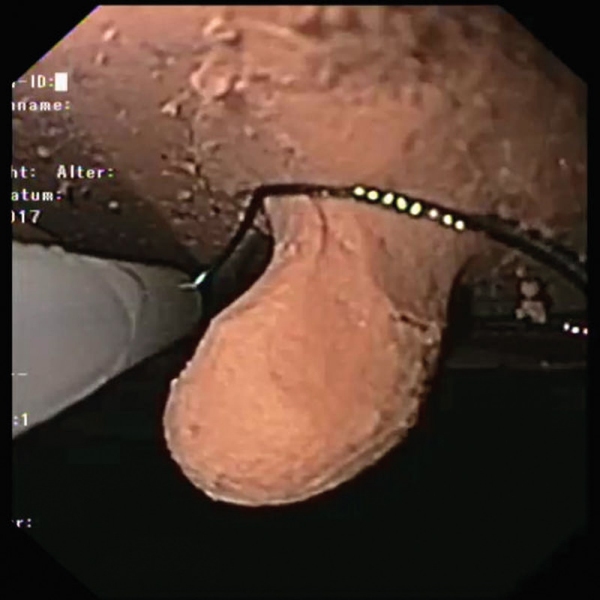

- Varikacijska ligatura

- Zdravljenje krvavitev / zaustavljanje krvavitev z injekcijami, sponkami in ligiranjem traku